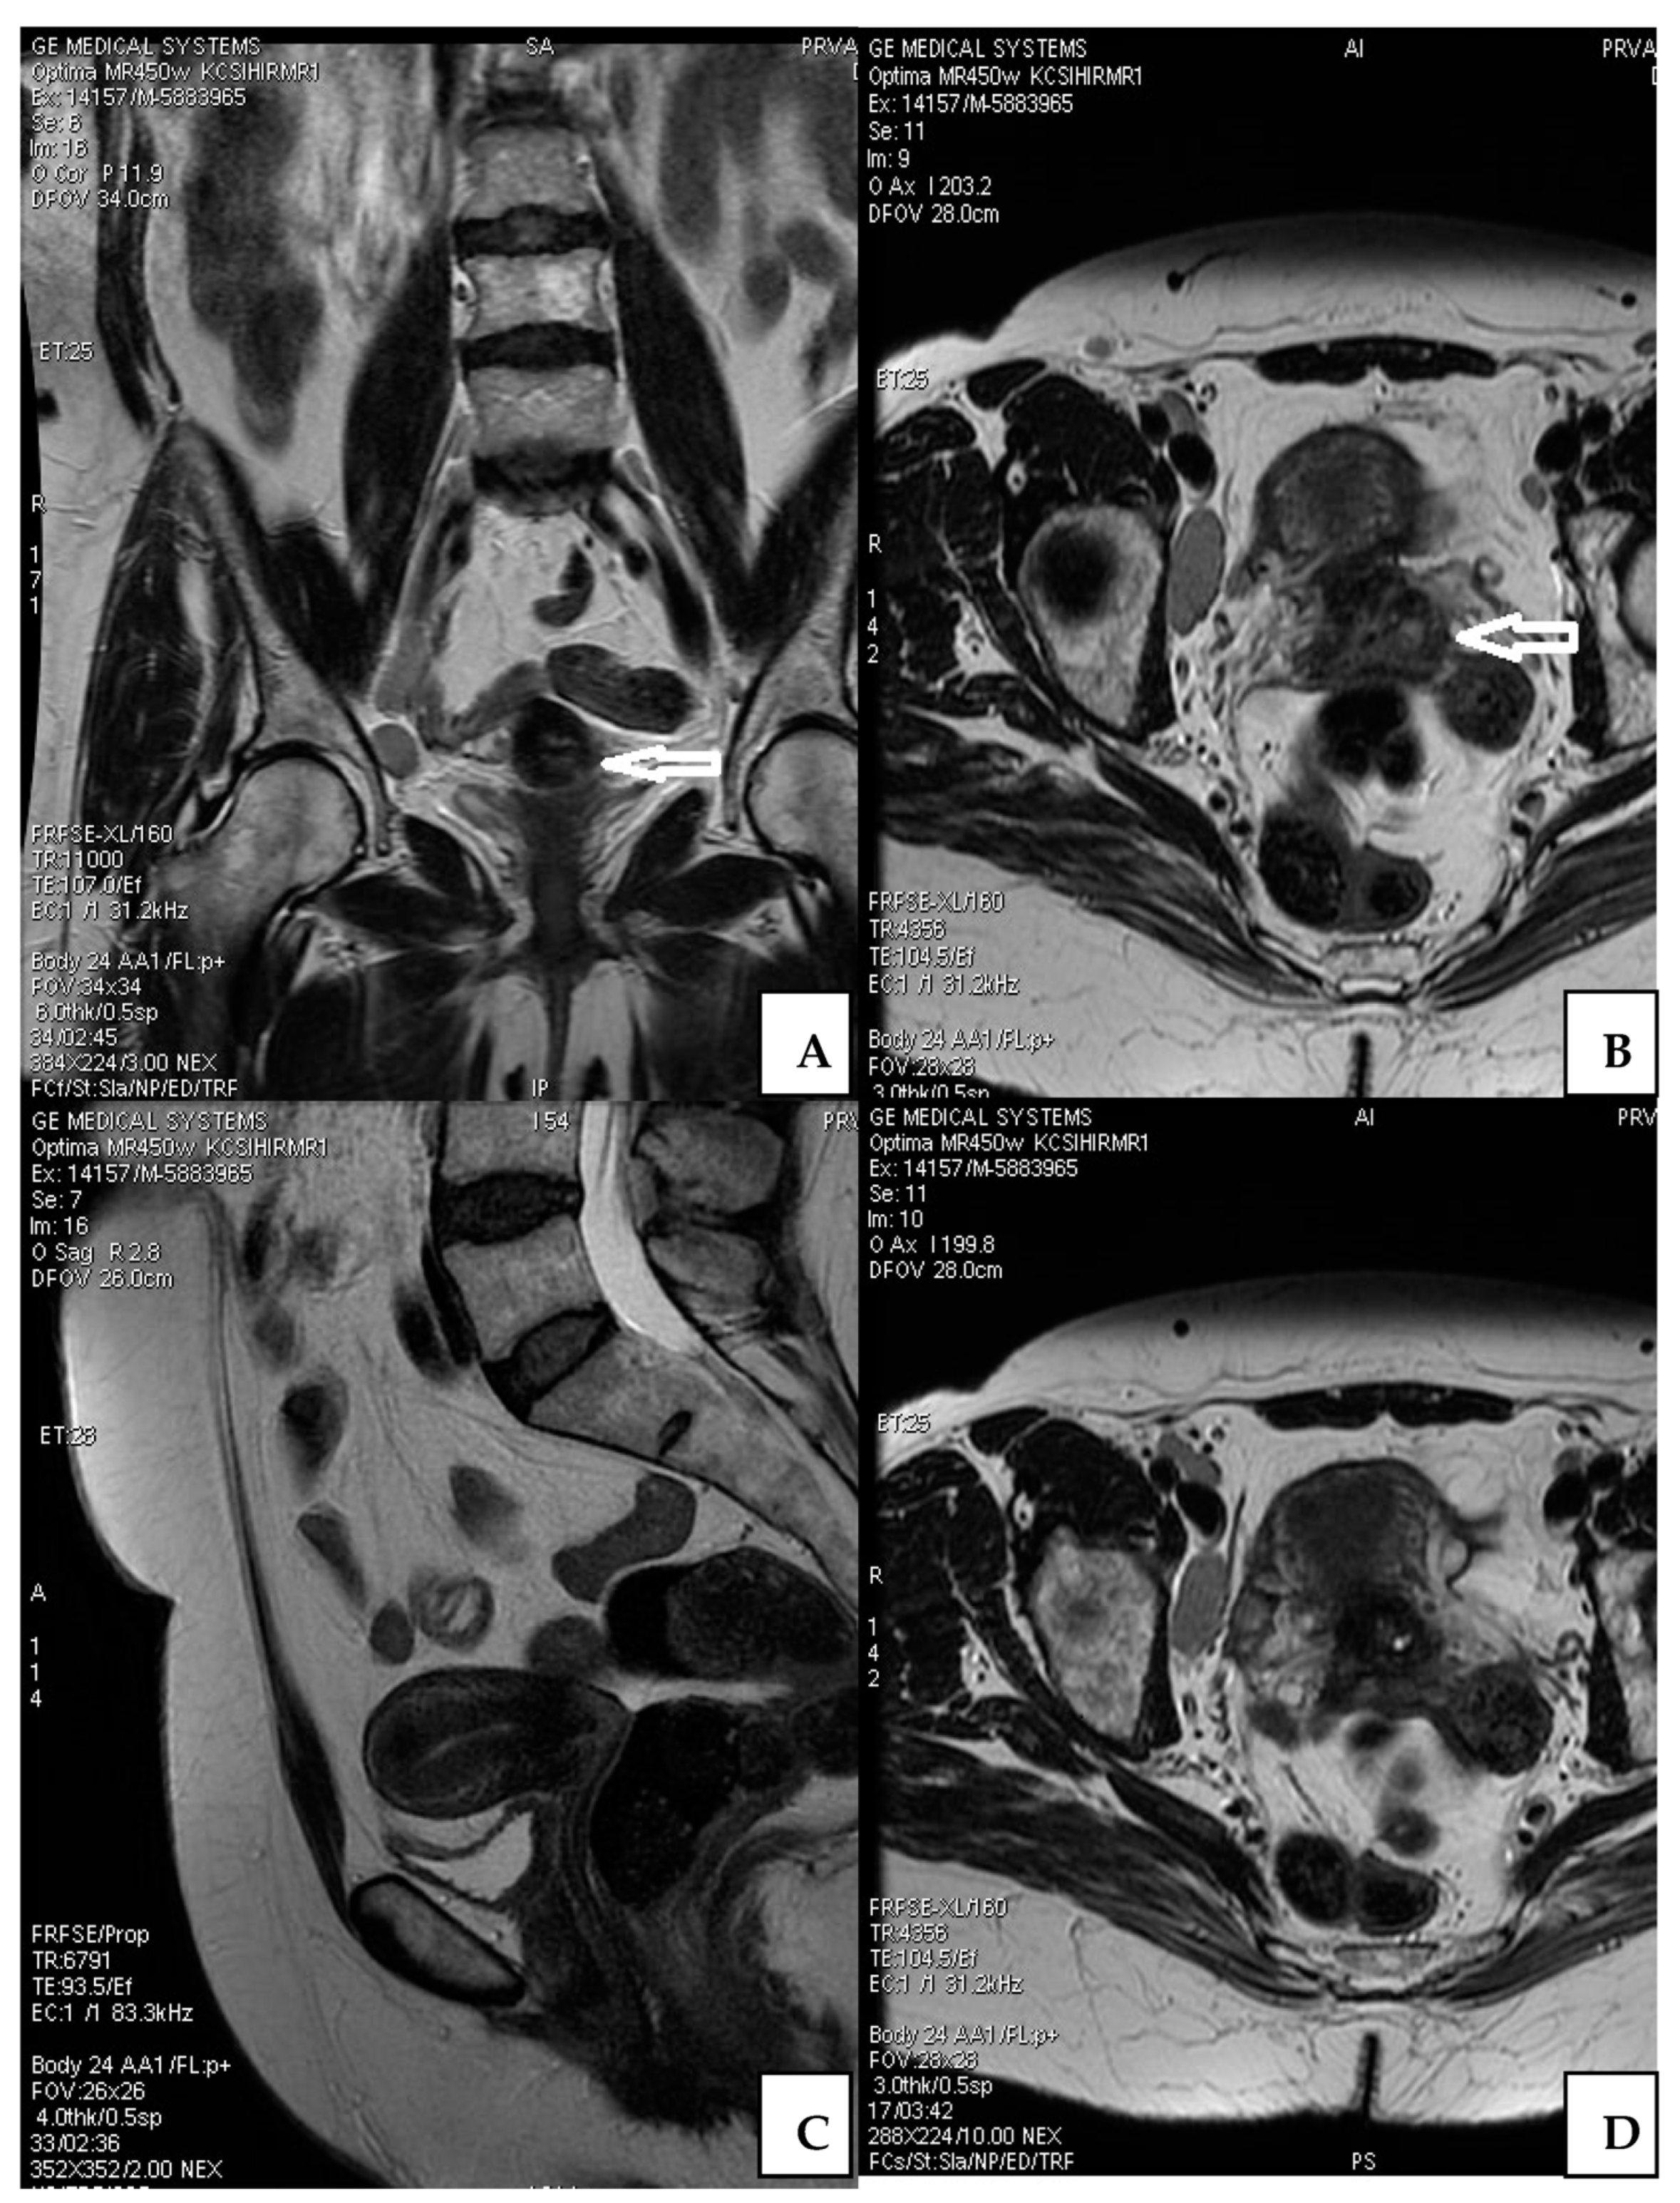

Abdomen and pelvis MRI examinations were conducted after conization, which showed a resting tumor in the cervical tissue (diameter 7 × 5 mm). The tumor spread to the proximal uterine segment without marked stromal infiltration. There was no tumor presence in parametrial tissue. The endometrium showed involutive characteristics. Many slightly enlarged lymph nodes were noticed, but without metastatic characteristics. Adnexal structures on imaging were not associated with suspected neoplastic lesions (Figure 1).

Figure 1. MRI of the abdomen and pelvis after conization. Cervical lesion (arrow) on diferent imaging presentations (A,B); Endometrium without detected tumor lesions (C); Adnexa without tumor lesion (D).